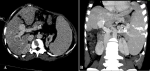

Diagnostic assessment: laboratory tests revealed microcytic hypochromic anemia (Hb 6.2 g/dL), low ferritin (6 µg/L), elevated C-reactive protein (11 mg/L), and positive HBs antigen. Doppler ultrasound demonstrated a saccular aneurysm with the characteristic 'yin-yang' flow pattern and mural thrombosis (Figure 1 A,B,C). CT imaging confirmed these findings, showing chronic partial thrombosis and marked splenomegaly with gastroesophageal varices (Figure 1 A,B).

Figure 2: contrast-enhanced abdominal CT in the portal phase: A) axial section showing a dilated portal trunk; B) coronal MIP reconstruction showing the intrahepatic portal vein aneurysm with mural calcifications